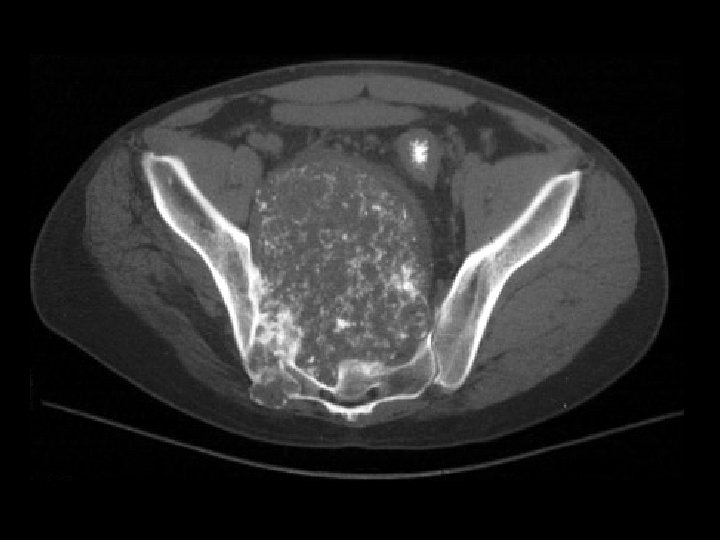

Chondrosarcoma • Findings: – Large bone-forming soft tissue mass centered in the right SI joint – “ring and arc Ca 2+” = calcified chondroid matrix • ddx: – NONE! – This is an Aunt Minnie!